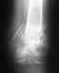

Консолидирующийся перелом внутренней лодыжки

Ходил два дня, на третий обратился к травмотологу. На снимке - закрытый перелом внутренней лодыжки со смещением отломков. Гипс 4 недели. По истечении 4 недель рентенограф (не тот, к-рый смотрел первоначально) заявляет: "Я не вижу следов сращивания кости". Заключение - Консолидирующийся перелом, граница перелома практически неразличима. Мой вопрос: "А был ли собственно "мальчик"? Или мои кости обладают феноменальной регенерацией? Снимков на руках у меня нет. Не хочу обидеть ваших коллег, но сомнения, честно говоря присутствуют. Жду Ваших комментариев.